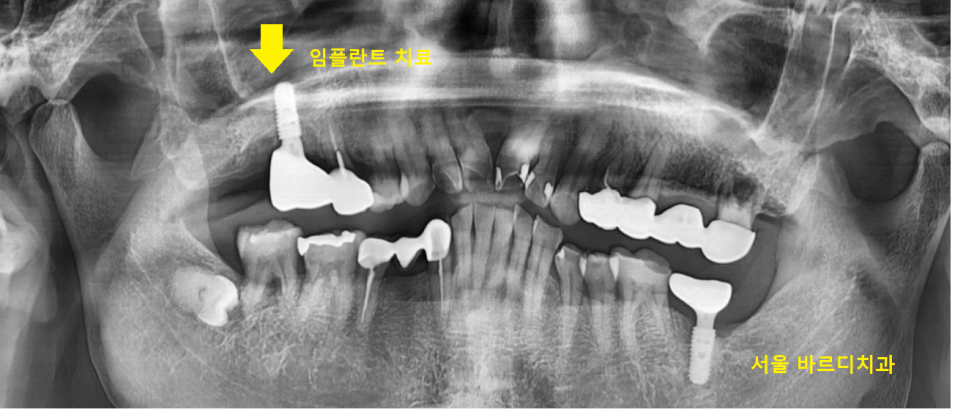

24.05.10

명일역 근처 치과에서 임플란트 완료한 사진입니다.

다른 부위도 안좋긴 하지만

급한 것부터 하나씩 하시기로 하셨는데요.

앞으로 관리 받으시면서

문제 있는 치아 바로 바로 치료하시기로 하고

치료를 완료해드렸습니다.

금니에서 치아 색깔로

심미적인 부분까지!

신경써드렸어요!~